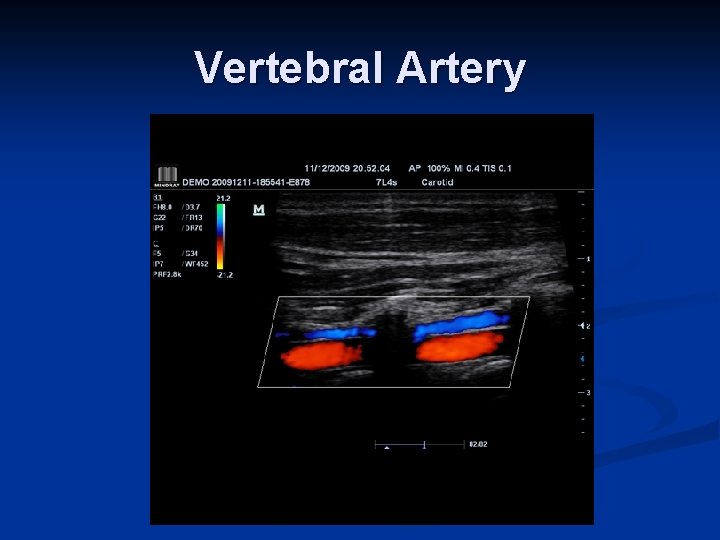

Vertebral Artery

Distinguishing characteristics of the vertebral artery: n First branch off subclavian n Enters foraminal canal at C 6 n Asymmetrical size: left > right n Low resistance flow